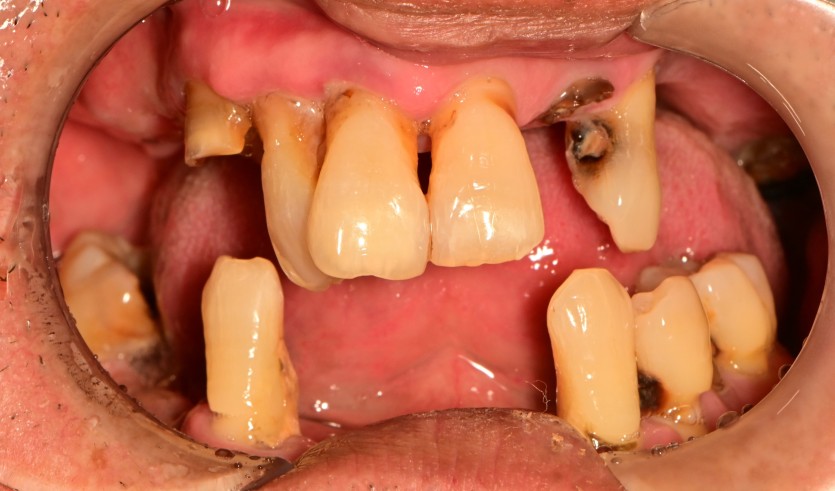

만 55세 전체 임플란트 증례

전체 임플란트 증례입니다.

18개의 임플란트로 완성하였습니다.